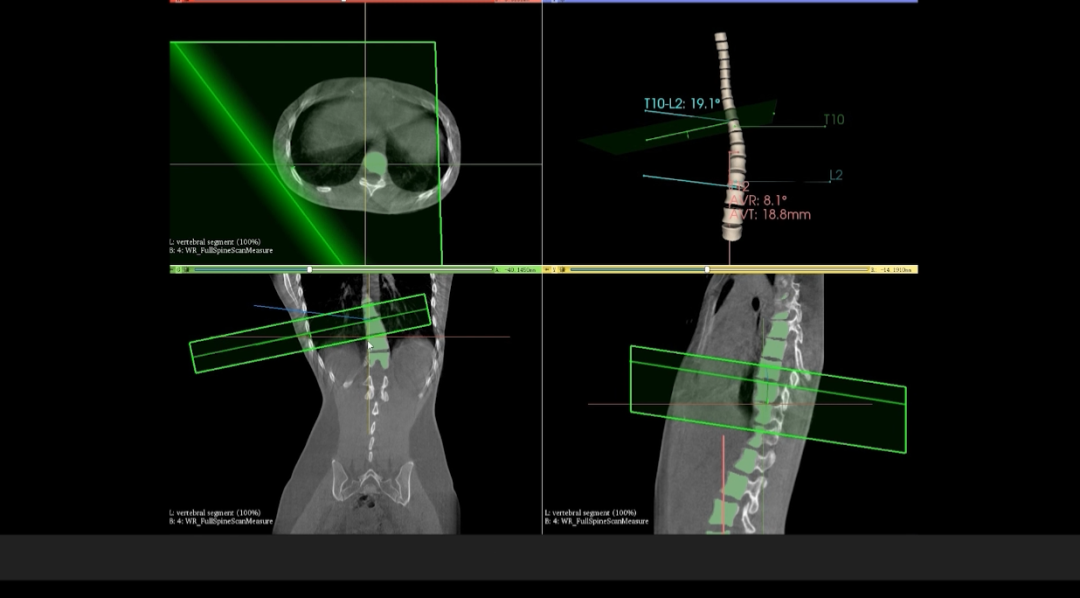

WR-3D它是一种基于CBCT的扫描方式并且能完成负重位状态下部位三维扫描与重建的全新技术,可支持三维影像扫描信息实时同步处理;值得一提的是,该技术完全基于数字化X线设备平台打造,剂量辐射水平远低于CT,同时也将原本DR的图像由二维扩展到三维,获得横断、矢状、冠状多方位图像。在临床诊断以及医疗方案制定中具有极大的价值意义。相较于普通平片下的负重位扫描,CBCT-DR能够避免二维状态下的组织结构重叠、密度分辨率不足、组织解剖结构难以分辨等问题,能全面地呈现被检查部位在多个角度下的三维影像信息,极大地降低了二维负重位检查带来的漏诊率。

在与华西医院开展的技术合作中,WR-3D的立位脊柱三维摄影技术能提供更加丰富的临床信息,通过WR-3D的三维全脊柱扫描与重建,即可完成脊柱三维影像重建,无需进行角度拼接,消除二维Cobb角度测量的误差,可以实现包括Cobb角、前/后凸角、椎体偏移/旋转向量图、椎体旋转角条形图、矢/冠状面垂直轴偏距数据的自动测量;这项技术将为脊柱矫形的临床诊断带来从定性到定量的转变,提供丰富的数据和图表,为临床尤其是手术方案的规划制定提供非常精准的定量化数据支撑,不仅可以对脊柱冠状面参数进行精准的定量评估,还可对矢状面包括,颈椎前凸、后凸、腰椎前凸和后凸进行非常精准的评估。